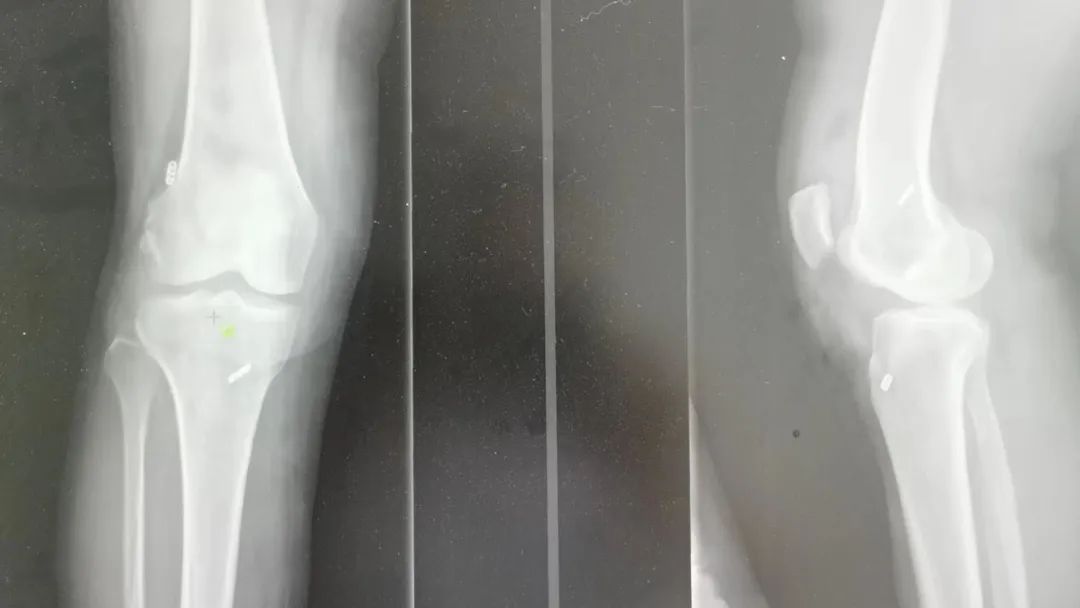

通过查体及辅助膝关节磁共振检查,明确诊断“右膝关节前交叉韧带断裂,外侧半月板撕裂”。